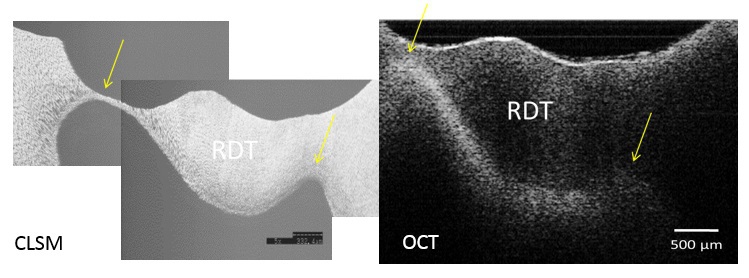

Methods: In the in vitro experiment, dentin discs including infected, affected and intact dentin were obtained from carious extracted human molars with visible occlusal cavities and scanned by a swept-source OCT at 1330nm center wavelength (Dental SS-OCT Prototype 2, Panasonic Healthcare). Attenuation coefficient (µt) and refractive index (n) were calculated for each dentin substrate. On a separate series of teeth, the remaining dentin thickness (RDT) was measured by OCT during removal of occlusal caries, and the results were compared to histological cross-sections using confocal scanning laser microscope (CLSM). In the in vivo experiment, OCT scans were obtained during excavation of occlusal caries to determine the type of dentin at the pulpal floor, and measure RDT.

Results: RDT values by OCT ranged from 140-2300µm. Pulpal horns and pulp chamber roof observation under OCT and CLSM resulted in comparable images that allowed measurement of dentin thickness; however, in the case of thick (> 2 mm) and/or caries-infected dentin tissue, the lower boundary of pulpal roof was occasionally masked due to higher µt values of infected dentin. Affected dentin showed slightly lower µt values than infected tissue. In terms of n, the following order was obtained; sound dentin>affected dentin> carious dentin. The clinical results confirmed the in vitro finding regarding the application of OCT.